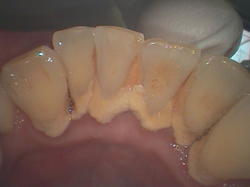

歯石を除去すると炎症を起こした歯肉が見えてきました。

ここから歯ブラシで歯肉を引き締めて行きます。